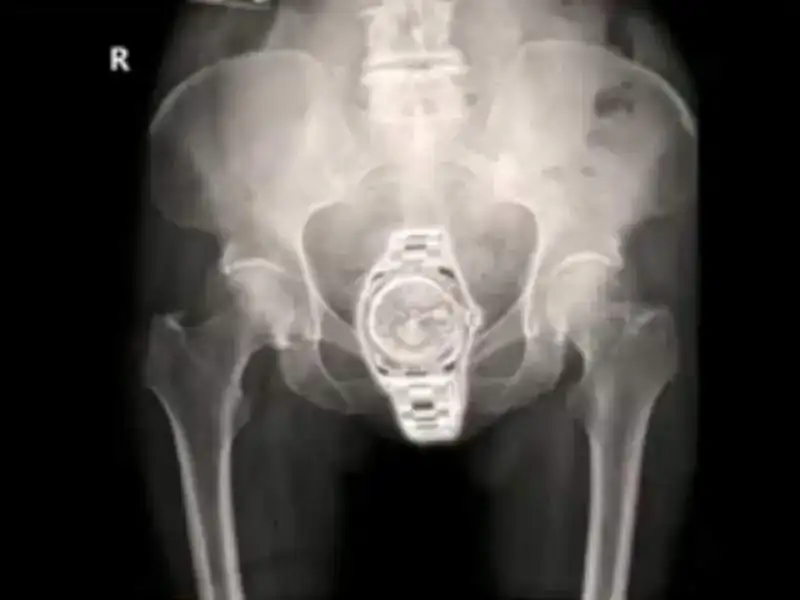

Si queréis moverlo al off-topic...pero aquí hay un reloj

Absolutamente falso pero no por las razones apuntadas si no porque la imagen se corresponde con la pelvis de un varón luego es imposible que el reloj fuera alojado en la vagina [emoji15] .

Tienes razón, ahora que me fijo mejor en la sinfisis pubiana veo que se trata de una mujer multipara, apendictomizada y con ovarios polisquisticos y no, no está en la vagina si no en una de las trompas de Falopio.quien ha dicho que esta en la vagina?

Concedo que podría tratarse de un hombre con un potorro.¿Por qué no puede estar en la vagina de un varón? Decir eso es dar un trato discriminatorio, o como se diga, a las mujeres, a los hombres y a los obispos/as. No solamente se trata de la vagina de un varón, sino que - además - ese varón es una mujer con toda la barba. ¡No sé cómo no te araño!